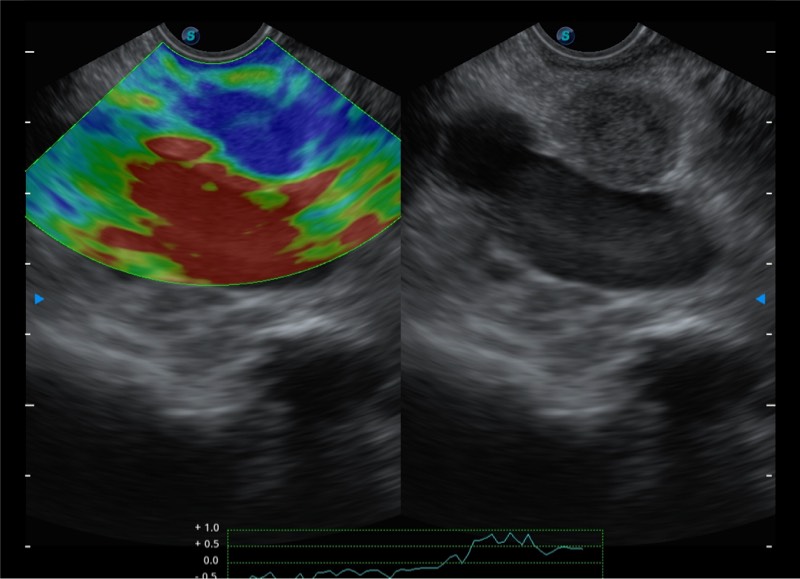

基于二十年的超声技术积累,狗万官方网站提供了最新一代的独立超声主机,在提供高质量图像的同时满足多学科使用。具备常见多普勒技术并提供弹性成像、声学造影等高端影像技术。新一代传感器具有更强的抗干扰能力并减少图像伪影。